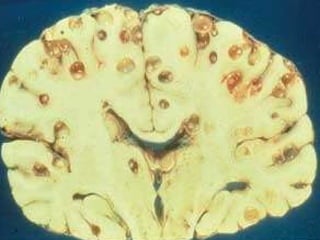

Au niveau du système nerveux La cysticercose atteint essentiellement le système nerveux central .  Le tissu nerveux oppose une réaction inflammatoire à l’infection qui, associée à la dégénérescence de la larve,  marque le début des signes neurologiques,  alors que la larve vivante reste cliniquement silencieuse.

Quatre localisations anatomiques sont décrites :   -  parenchymateuses  : les kystes habituellement inférieurs à 1 cm de diamètre, sont localisées dans les hémisphères cérébraux, c’est l’atteinte la plus fréquente, plus de 60% des patients

intra ventriculaires les kystes sont trouvés surtout dans le IVème ventricule, un peu moins souvent  dans les ventricules latéraux, elles représentent 10 à 20% des patients atteints

sous-arachnoïdiennes les kystes peuvent atteindre 10 cm et plus, car leur développement n’est pas limité par la pression intracérébrale, - spinales ou médullaires, localisées soit dans la moelle, soit dans les espaces arachnoïdiens.

La cysticercose «racémeuse» est caractérisée par une prolifération de kystes lobulés en «grappes de raisin», sans scolex, habituellement située dans le système ventriculaire et les espaces sous-arachnoïdiens

Au niveau dusystème nerveux La cysticercose atteint essentiellement le système nerveux central . Le tissu nerveux oppose une réaction inflammatoire à l’infection qui, associée à la dégénérescence de la larve, marque le début des signes neurologiques, alors que la larve vivante reste cliniquement silencieuse.

Quatre localisations anatomiquessont décrites : - parenchymateuses  : les kystes habituellement inférieurs à 1 cm de diamètre, sont localisées dans les hémisphères cérébraux, c’est l’atteinte la plus fréquente, plus de 60% des patients

intra ventriculaires leskystes sont trouvés surtout dans le IVème ventricule, un peu moins souvent dans les ventricules latéraux, elles représentent 10 à 20% des patients atteints

sous-arachnoïdiennes les kystespeuvent atteindre 10 cm et plus, car leur développement n’est pas limité par la pression intracérébrale, - spinales ou médullaires, localisées soit dans la moelle, soit dans les espaces arachnoïdiens.

La cysticercose «racémeuse»est caractérisée par une prolifération de kystes lobulés en «grappes de raisin», sans scolex, habituellement située dans le système ventriculaire et les espaces sous-arachnoïdiens